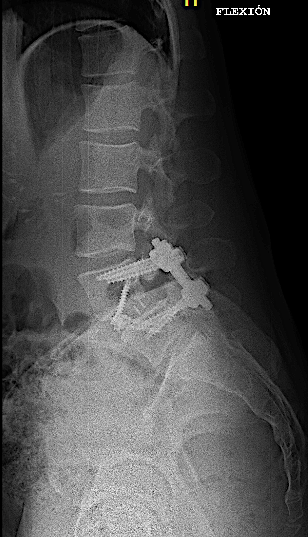

Obsérvese el incremento de la lisis de la pars en las RX dinámicas. La paciente no presentaba clínica radicular significativa por lo que se optó por ALIF L5-L6. El disco L4-L5 presentaba un grado bajo de degeneración.

Tras retirada de faja, la paciente seguía presentando lumbalgia mecánica. Obsérvese la lisie de la pars.